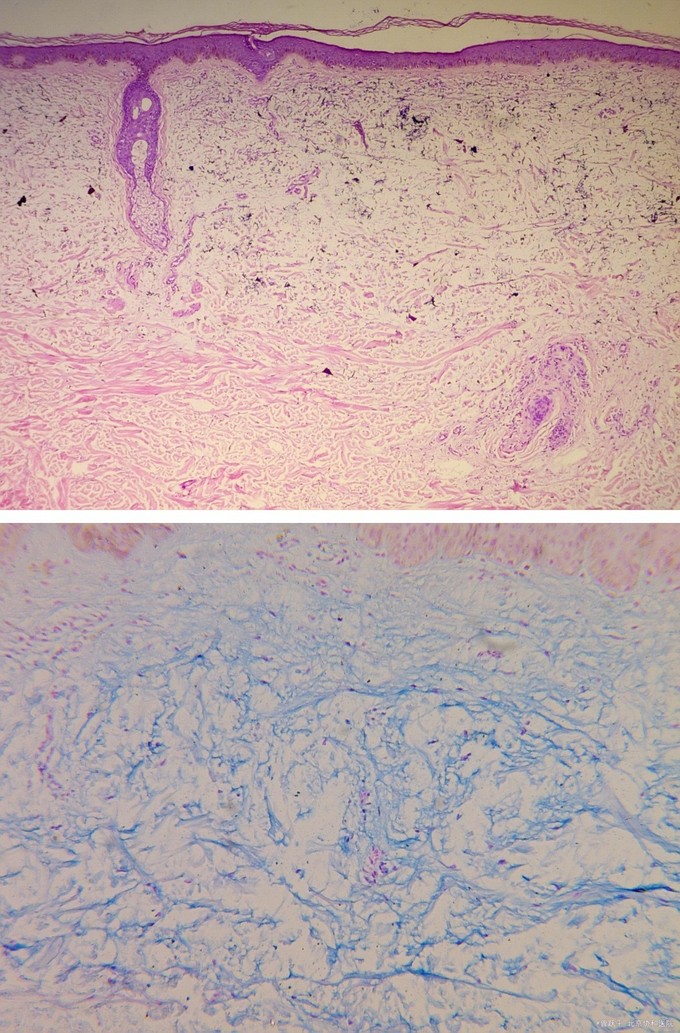

一般情况良好,系统检查无异常。 双手背、腕部及双前臂远端伸侧、项部可见对称性散发圆顶丘疹,1-5mm大小,半透明至肤色。项部左下方可见一1cm×1.5cm大小红色斑块。所有皮损表面光滑、质韧,无触痛。 其余部位皮肤未见类似损害。 血尿常规、肝肾功能、甲状腺功能、血清蛋白电泳和免疫蛋白电泳检查未见异常。 组织病理(左前臂和项部丘疹):表皮大致正常,真皮浅中层带状粘蛋白沉积,胶原纤维间隔显著增加。安申兰染色阳性。